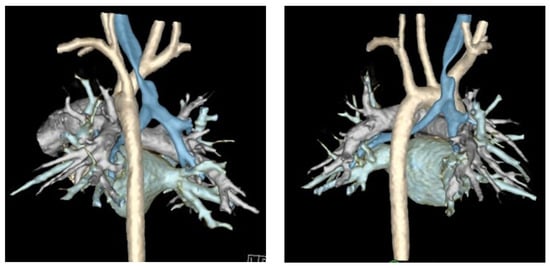

Finally, computed tomography (CT) of the chest with intravenous contrast should be obtained preoperatively to evaluate the great vessel, spinal, tracheal, esophageal, and lung parenchymal anatomy [15,22,29,32,33,38]. Preoperative findings, such as tracheal diverticula, transverse tracheal/bronchial malformations, anterior tracheal compression, or otherwise aberrant anatomy, may redirect surgical plans to involve resection, external splinting, or a combination of these procedures [10]. Cross-sectional imaging methods including Dynamic Volumetric Computed Tomography Angiography (DV-CTA) and contrast-enhanced multidetector computed tomography (MDCT) are preferable for the diagnosis TM/TBM, as they can evaluate the luminal dimensions at both end inspiration and end expiration [5,13,15,19,21,33,34,40,41]. Dynamic airway MDCT and DV-CTA have up to a 91% diagnostic correlation with bronchoscopy [37,41]. Luminal area reduction of >50% during expiration has traditionally often been used as a cutoff for the diagnosis of TM/TBM, and the location of luminal narrowing seen on CT can further be used to guide precise tracheopexy (Figure 3) [19,40,41]. Traditional CT with IV contrast may also be used to measure the lateral and anterior–posterior diameter of the trachea (LAR) at the level of the innominate artery to quantify the severity of tracheal collapse, a metric that has been used to evaluate postoperative outcomes as well [42]. Preoperative cross-sectional imaging also allows for early detection of extrinsic compressions of the trachea by mediastinal masses, descending aorta, vascular rings, or otherwise anomalous cardiovascular anatomy [6,15,38,43]. These should be denoted preoperatively, as this may require involvement of pediatric cardiothoracic surgeons to perform complex vascular reconstructions while the patient is on cardiopulmonary bypass (CPB) [43,44]. Comprehensive workup identifying primarily posterior compression and/or intrusion of the pars membranacea indicates the patient may be a good candidate for posterior tracheopexy [16,20,24,25,45,46].

Figure 3.

Three-dimensional reconstruction of dynamic airway CT scan. Trachea is highlighted in blue and aorta is highlighted in off-white/cream.